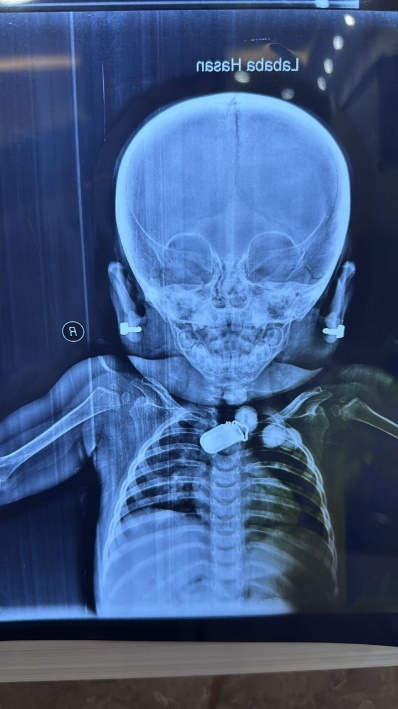

Figure 2: Hands and feet deformities

Short, broad hands and feet with clenched fingers and bilateral clubfoot, consistent with skeletal anomalies described in HPMR

Skeletal: Short broad hands/feet, clenched fists, bilateral clubfoot.

Figure 11: Skeletal deformities of the upper and lower limbs

Photographs showing short, broad hands with clenched fingers (upper image) and bilateral clubfoot deformities (lower image), consistent with skeletal abnormalities described in HPMRS.